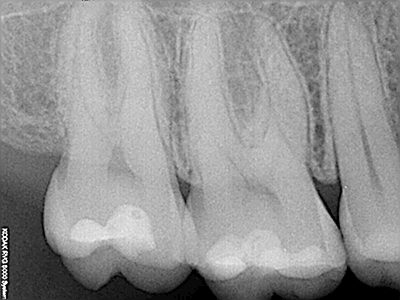

NUESTROS CASOS:

Endodoncia

Capielo